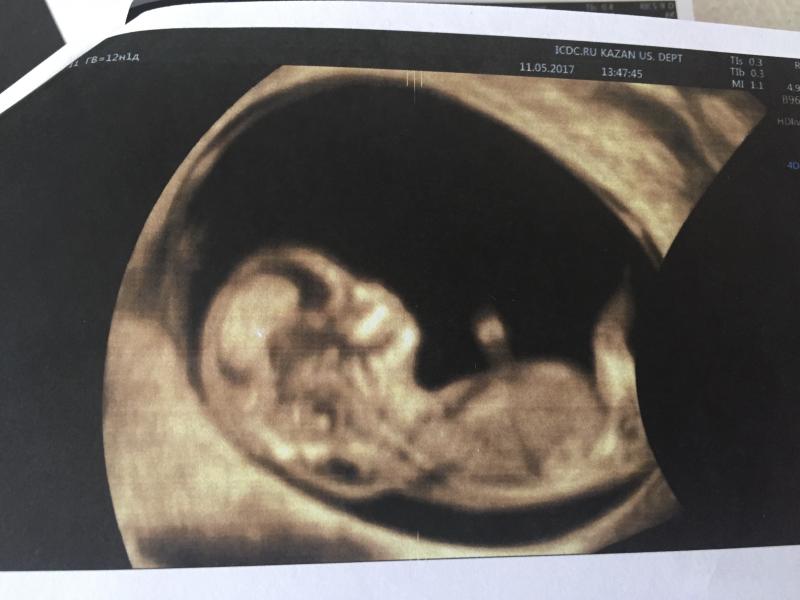

❗️SOS❗️Делюсь с вами фото моей крохи. Прошла УЗИ-скрининг 1-го триместра. Радостно что живой, сердце бьется, но ❌поставили в группу риска на хромосомные аномалии ❌т.к. Увеличена толщина воротникового пространства ( видно на фото ) 3,8мм и укорочён нос 1,8 мм. Будем сдавать кровь из вены ( панорама тест). Срок 12 недель и 1 день. А пока хочу спросить. У кого так было? Что делали и чем дело кончилось? Очень боюсь

@rezeda02, на УЗИ можно конечно дополнительно, но даже по фото видно, что воротник толстый - просто надеюсь что все придёт в норму или на "так бывает"

@nika_035, да, вот кровь теперь сдать надо. Но воротник у нас и правда толстый, даже на фото видно